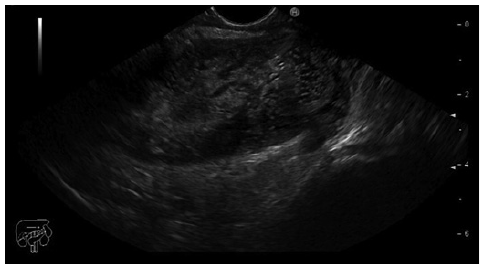

Prior to the puncture, the PFC was carefully evaluated for size and location, ensuring the collection was within 1 cm from the rectosigmoid wall and that no intervening blood vessels would impede the procedure. An electrocautery-enhanced LAMS delivery system (Hot-Axios®; Boston Scientific, Marlborough, MA, USA) with a stent diameter of 15 or 20 mm was used based on the endoscopist’s discretion and availability at the time of the procedure. The ERBE VIO 200D electrosurgical unit, using AUTOCUT mode, effect 5, power 100 W, was employed for the transrectal puncture with the Hot-Axios® system. The direct puncture technique was performed under EUS guidance alone (without fluoroscopic assistance). The distal phalanx deployment was executed under ultrasound visualization, while the proximal phalanx release was conducted with endoscopic or/and ultrasound view (Fig. 1, 2).